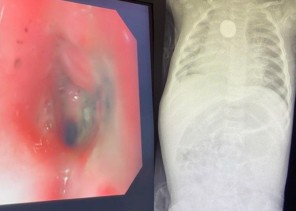

احتفى مستشفى الولادة والأطفال بتجمع مكة المكرمة الصحي ممثلاً بمركز أورام الأطفال بالمستشفى وبالتعاون مع جمعية براءة لأمراض دم وسرطان الأطفال بشفاء 50 طفلاً من مصابي سرطان الدم.وتضمن الحفل معرضاً مصاحباً بمشاركة مركز أورام الدم ...